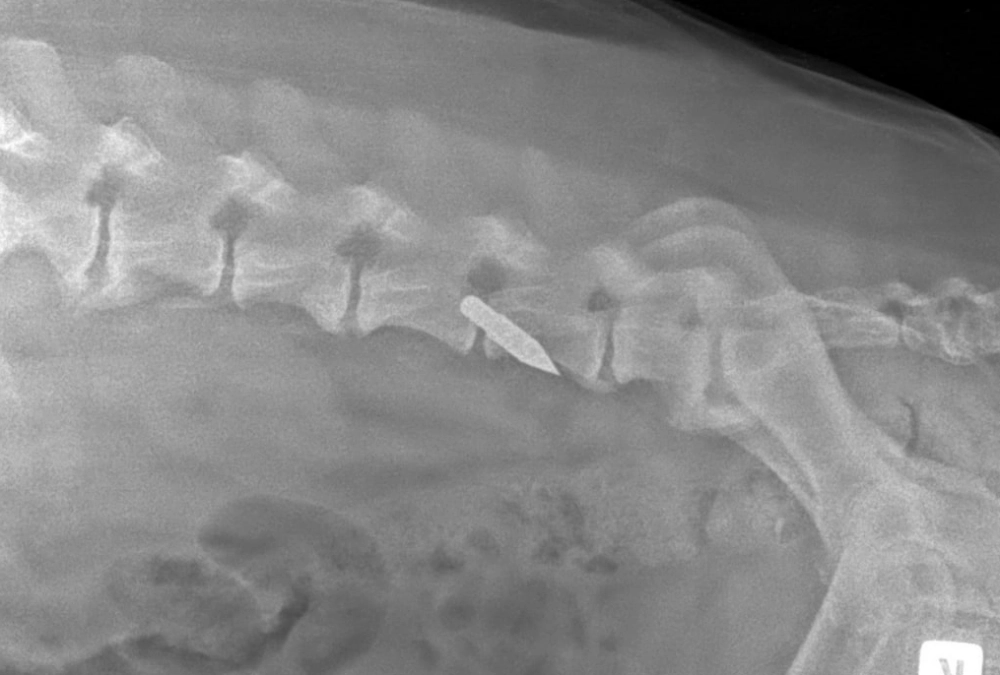

После первичных осмотров и перевязок ветеринары и добровольцы были удивлены состоянием пса: несмотря на тяжелые раны, температура была в норме, а анализы не выдавали критических отклонений. Рентген показал, что жизненно важные органы не задеты.

Первая ночь в клинике была напряженной как для пса, так и для ветеринаров. Операция закончилась лишь в третьем часу ночи. На хирургическом столе выяснилось, что ранее собаке уже удавалось чудом выжить с серьезными травмами — у пса обнаружили застарелый разрыв селезенки и гематому на почке. Но на этом «сюрпризы» не закончились.